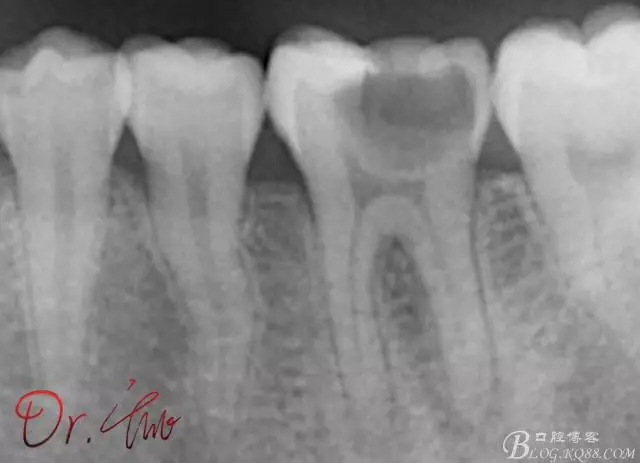

第一次試主尖

640.webp (2).jpg

第二次試主尖

640.webp (3).jpg

根充

640.webp (4).jpg